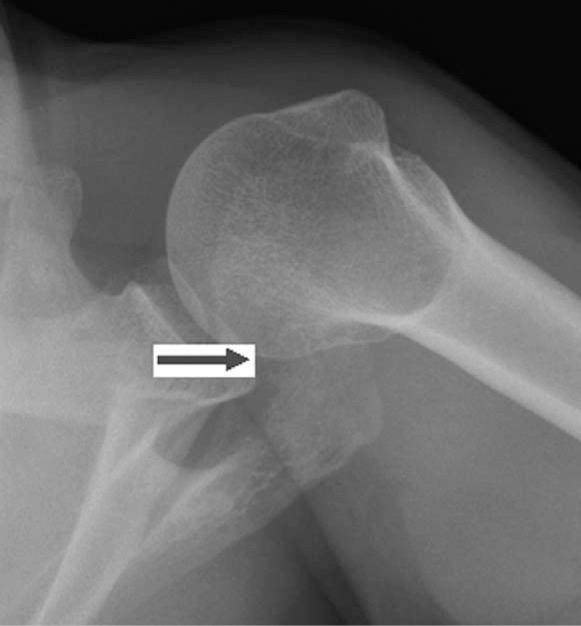

Os acromiale as a cause for shoulder pain in a competitive swimmer: a case report.

Sports Health. 2009 Mar;1(2):121-4. doi: 10.1177/1941738108326705.